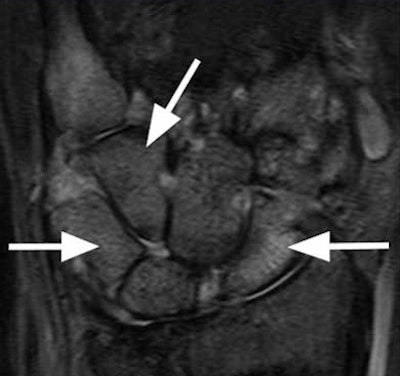

| Images show bone marrow edema in 31-year-old woman with rheumatoid arthritis. Extremity MRI (above) and conventional MRI (below) both show extensive and comparable edematous changes throughout the carpal bones (arrows). Images courtesy of Radiology. |

The readers' image analyses demonstrated "almost perfect agreement between the results on the extremity and conventional MR systems for both readers with regard to bone erosion, synovitis, bone marrow edema, and total scores," the study noted. "Intraclass correlation coefficients were highest for erosion, bone marrow edema, and total scores, but even the synovitis scores demonstrated high agreement between the two systems."

On the basis of those observations, the researchers concluded that "inflammatory and destructive changes in rheumatoid arthritis are equally well demonstrated with the 1T extremity MR system as with the conventional 1.5T system."

They also added that the 1-tesla extremity system demonstrated "excellent correlation with the 1.5T conventional system, with respect to demonstration of bone marrow edema and synovitis, features that have been problematic for 0.2T extremity systems."